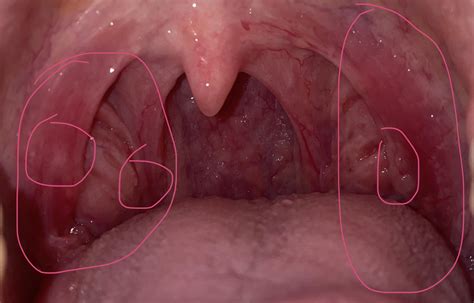

• Tonsilloliths (Tonsil Stones): Perhaps the most common culprit. These are calcified accumulations of food particles, bacteria, and mucus that get trapped in the small crevices of the tonsils.

• Tonsillitis: Often caused by viral or bacterial infections (like Strep throat), this condition can cause white, pus-filled patches or bumps on swollen tonsils.

Distinguishing Between Common Conditions

Because symptoms often overlap, it can be difficult to self-diagnose. The following table provides a quick reference to help distinguish between these common causes based on typical characteristics.

Condition Primary Appearance Common Associated Symptoms

Tonsil Stones Hard, white/yellowish particles Bad breath, sensation of something stuck

Tonsillitis White/yellow pus patches Sore throat, fever, difficulty swallowing